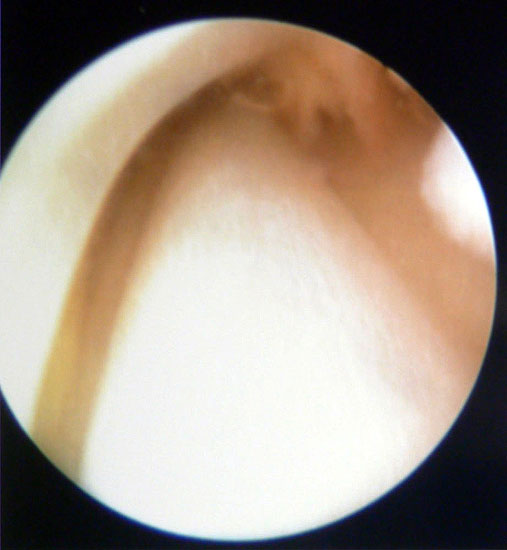

Tendoskopie der Peronealsehnen. Aufgrund der engen Raumverhältnisse sind die therapeutischen Möglichkeiten limitiert.

Abbildung 7

Die Tendoskopie bietet eine weitere Möglichkeit Sehnenpathologien zu visualisieren. Dieses invasive diagnostische Verfahren hat angesichts der immer höher werdenden MRT-Auflösung und den Möglichkeiten der dynamischen Untersuchung mit hochfrequenten Ultraschallköpfen keine größere Verbreitung erfahren. Die therapeutischen Möglichkeiten des Verfahrens beschränken sich auf eine lokale Synovektomie, die Lösung von Verklebungen und dem Abtragen von Knochenkanten 13141516.